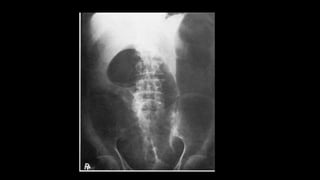

X-ray abdomen-supine

Gastric dilatation

Causes

• Paralytic ileus

• Mechanical bowel obstruction

• Gastric volvulus

• Air swallowing